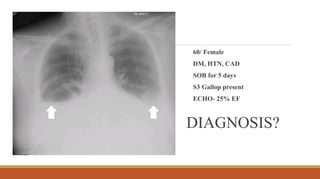

60/ Female

DM, HTN, CAD

SOB for 5 days

S3 Gallop present

ECHO- 25% EF

DIAGNOSIS?